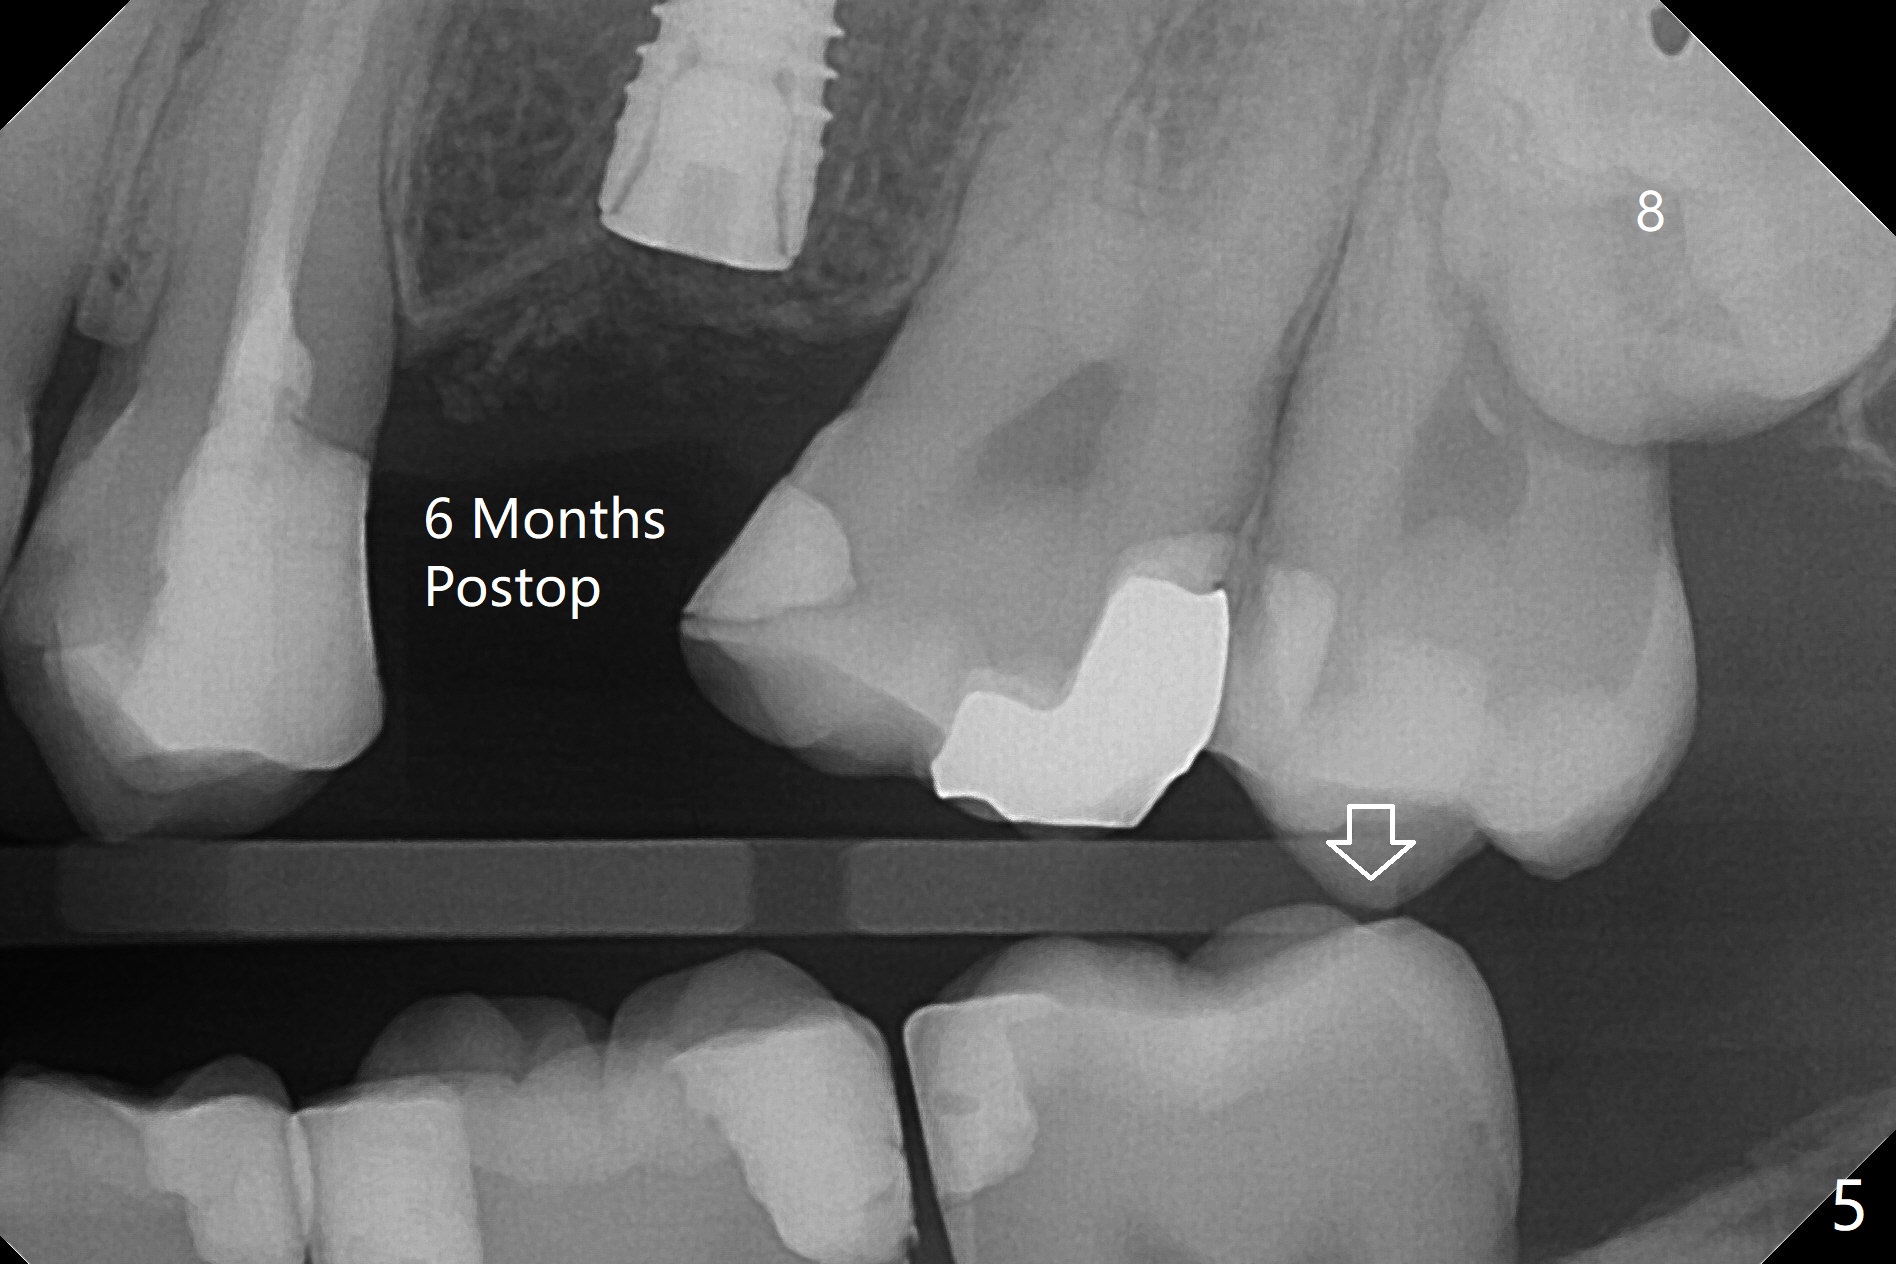

术后6个月植体愈合正常,但是6,7号牙好像前移(图五),切开,放置4.5x5(3)毫米愈合基台,必须磨去6号牙近中树脂(图七:<)。8阻生牙可能迫使7延长(图五:箭头),可能造成前牙开合(图六:*),6,7牙根之间几乎没有骨质。